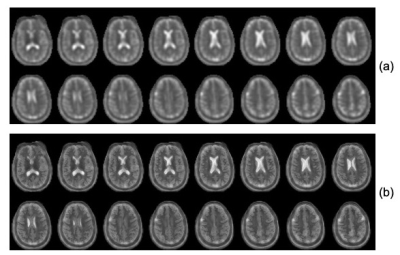

Figure 2: (a) Selected partitions from a 3D SW TPI sodium image acquired on a healthy human brain (TE/TR=0.3/100ms, 1596 views). (b) Selected partitions from the AGR sodium reconstruction of the data set presented in figure 2a. Note the significant improvement in spatial resolution, which allows depiction of differences in tissue sodium concentration between gray and white matter.